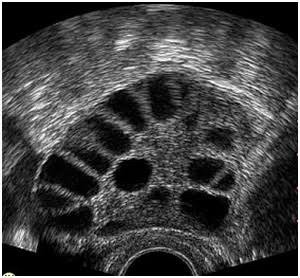

มีเคล็ดลับมาบอกสำหรับแม่ๆที่มีบุตรยาก ก่อนหน้านี้ตัวเองเป้นPcos ไม่เคยคิดว่าจะมีลูกได้ จนมาเจอตัวนึงที่ทำให้ตัวเองมาถึงวันนี้❤️